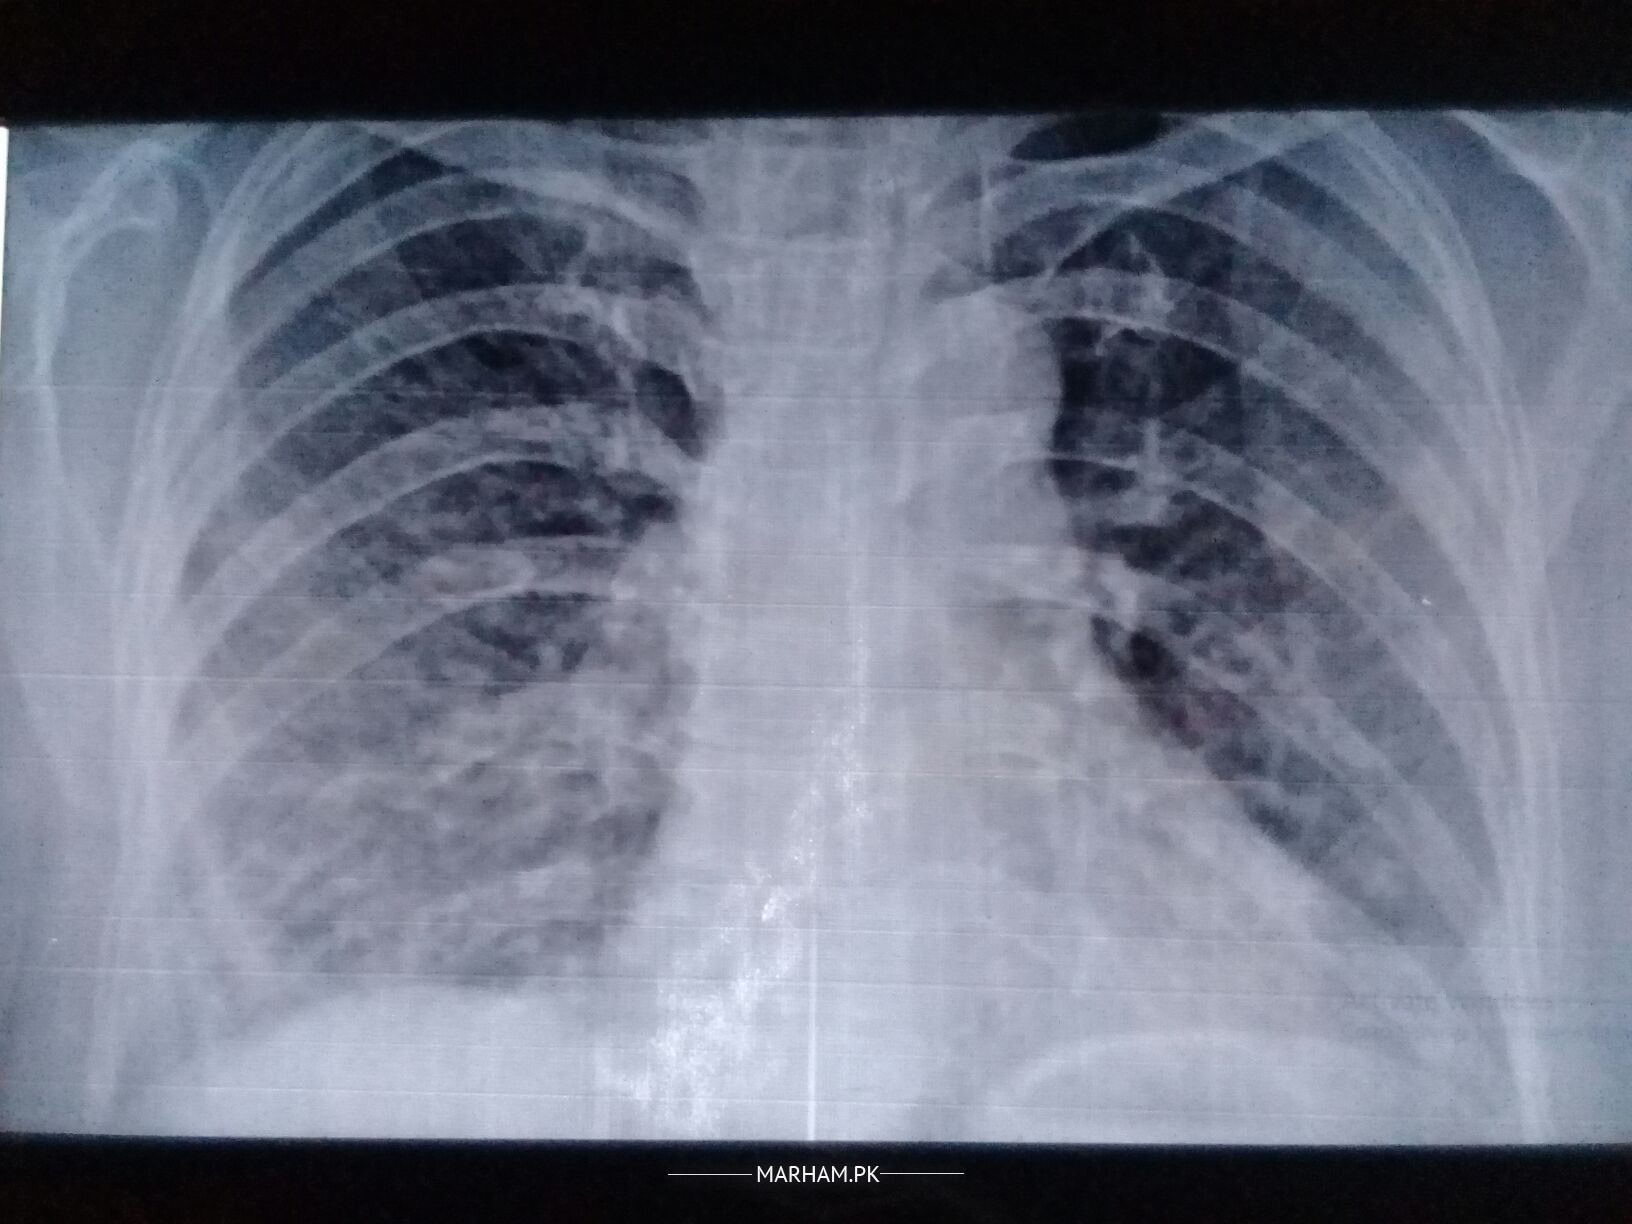

Please check these reports

pehle unhe fever, flue, or body pain rahe hain 10 days k liye but ab inhe cough hai 17 may say ye medicine lay rahe hain medicine prescribed by pulmonologist: 500 mg azithromycin 2 time for 15 days, risek 20 mg 2 time, myteka and softin at night, and nebulization with clenil and atem, syp britanyl 1/2 sp 3 time for 15 days

these symptoms relates to corona as afb is negative,so the prescribed medicine are you should also go for covid test.

Due to current pandemic most likely she is covid positive xrays and crp are also suggestive of covid

Seems to be a covid caseXRay taken on2/5 shows improvement. Duration and dose of Azithromycine needs to be reduced test of the treatment seems ok.